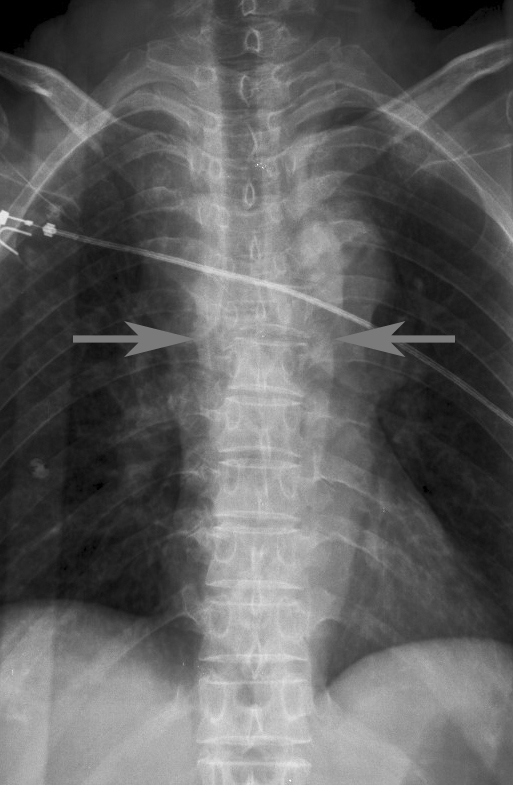

Gallery Blunt Chest Trauma Spine trauma Case 1b

Case 1b